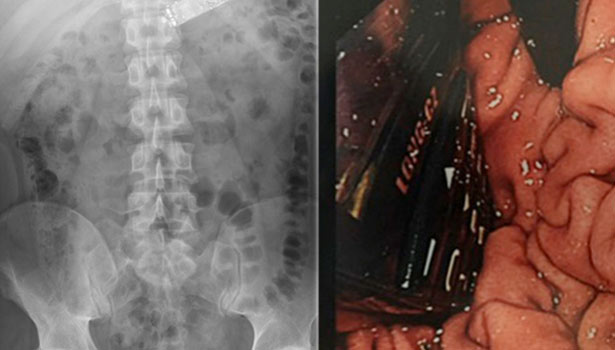

எண்டோஸ்கோப் மூலம் ஒரு நீண்ட மெல்லிய நெகிழ்வான குழாயின் வழியாக ஒளியைப் பாய்ச்சி வீடியோ கேமராவின் வழியாக பார்த்தபோது, உணவுக்குழாயின் இடையில் அவரது வயிற்றுக்குள் செல்போன் சிக்கி இருப்பதை டாக்டர்கள் கண்டறிந்தனர்.

செல்போனை விழுங்கிய பத்துமணி நேரத்துக்கு பின்னர் வயிற்றின் பக்கவாட்டில் அறுவை சிகிச்சை செய்து, அந்த செல்போனை மருத்துவர்கள் வெளியே எடுத்துள்ளனர். சுமார் ஒருவார மருத்துவ கண்காணிப்புக்கு பின்னர் அவன் சிறைச்சாலைக்கு அனுப்பி வைக்கப்பட்டதாக சர்வதேச மருத்துவ ஆராய்ச்சி கையேடு (International Journal of Surgery Case Reports) வெளியிட்டுள்ள செய்திக்குறிப்பில் தெரிவிக்கப்பட்டுள்ளது.